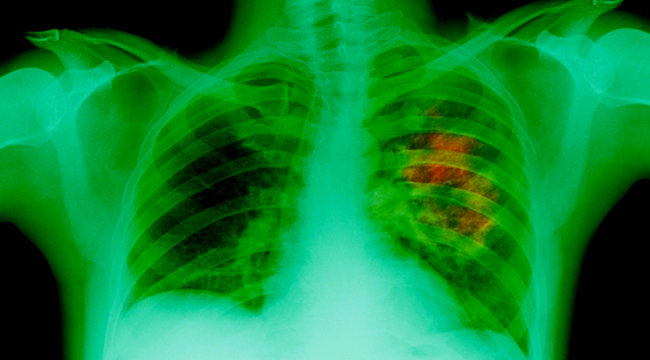

When radon is inhaled, its radioactive particles can get trapped in your lungs. As time passes by, these cancer-causing particles will increase the risk of lung cancer. Moreover, those who smoke and inhale radon gas at the same time are at a greater risk of developing lung cancer. In fact, radon causes about 15 percent of lung cancers all over the world, according to the World Health Organization (WHO).